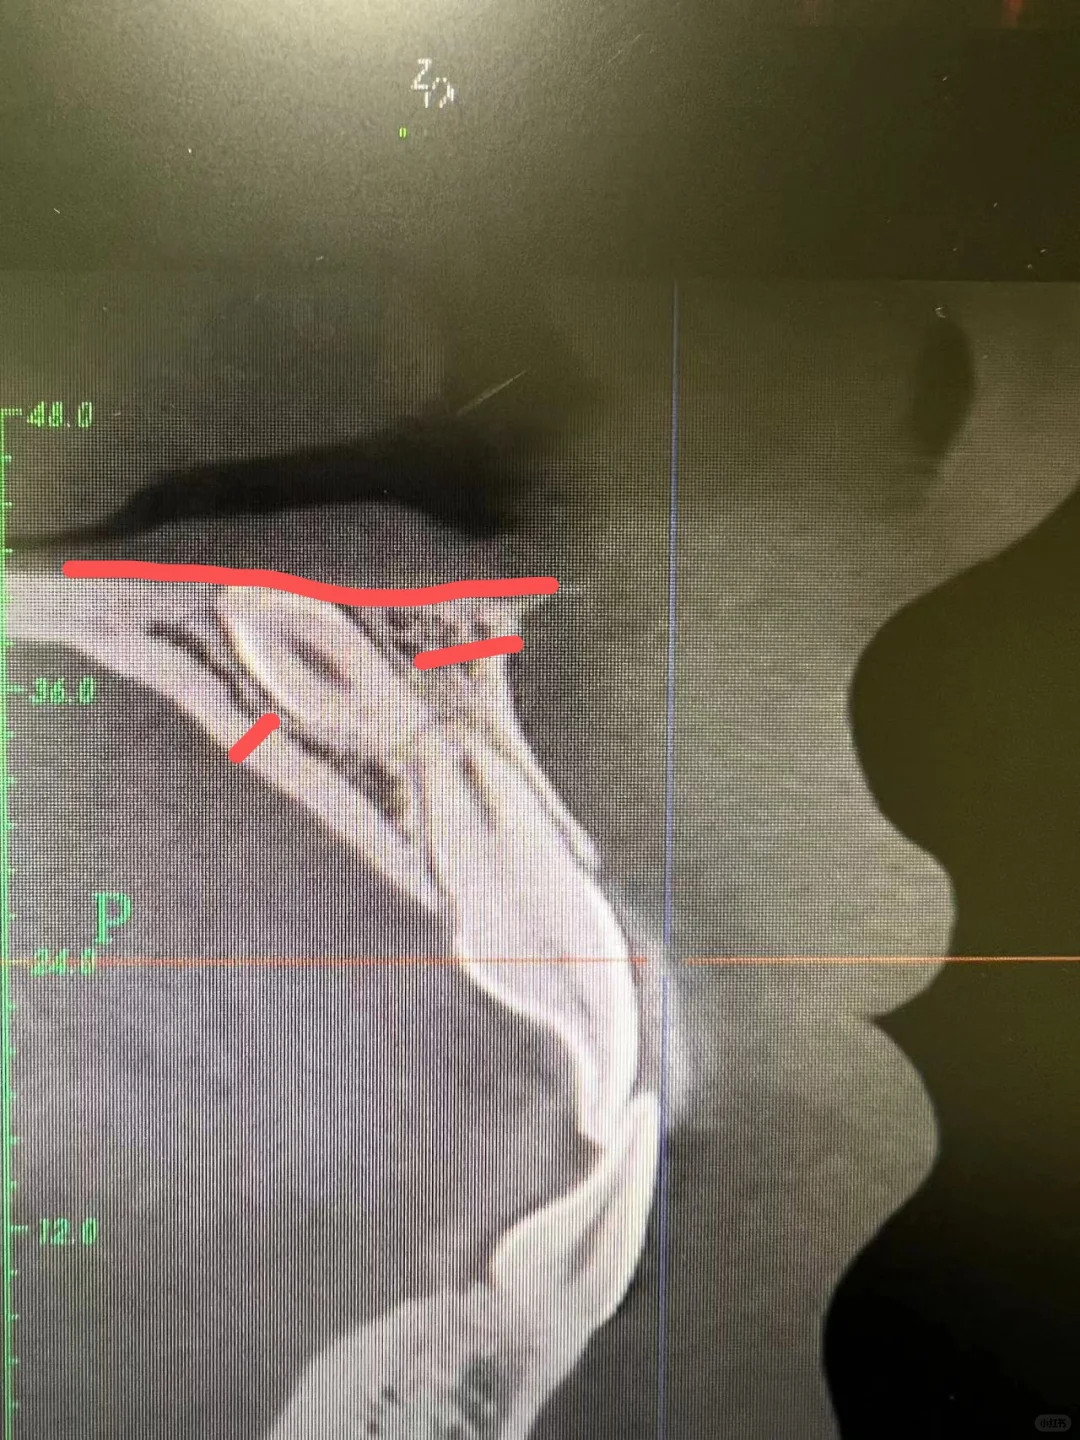

**口腔叫来我们医院口腔科拔掉,再回去矫正,恰好我接了,拍了cbct发现这颗牙倒着长的,牙尖在鼻腔底了,关键无论是唇侧还是腭侧,骨头都很厚,非常难拔!

最后还是选择从腭侧开口进去拔牙,用了差不多一个小时的时间,收了1800块钱,这是我半年来拔的最贵的一颗牙齿🦷了!